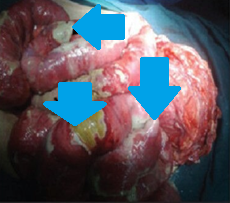

Εξερευνητική λαπαροτομία – Πολλαπλές διατρήσεις σε άλλο ασθενή με οζώδη πολυαρτηρίτιδα. Ευγενική παραχώρηση Dr. V. Penopoulos.